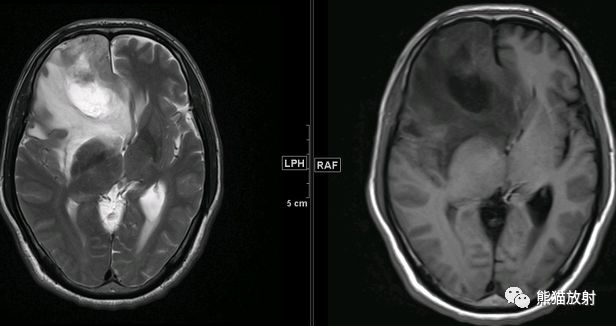

mr图谱 放射性脑损伤vs 胶质瘤复发 知乎